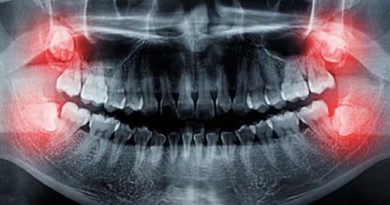

Bien que les dents permanentes soient censées durer toute la vie, il existe un certain nombre de raisons pour lesquelles l’extraction d’une dent peut être nécessaire. Une raison très courante est qu’une dent est trop endommagée, à la suite d’un traumatisme ou d’une carie, pour être réparée. Parmi les autres raisons, on peut citer :

Parfois, les dentistes enlèvent des dents pour préparer la bouche à l’orthodontie. Le but de l’orthodontie est d’aligner correctement les dents. Cela peut ne pas être possible si vos dents sont trop grandes pour votre bouche. De même, si une dent ne peut pas percer la gencive (éruption) parce qu’il n’y a pas de place dans la bouche pour elle. Votre dentiste peut vous recommander de l’extraire.

Si la carie ou les dommages s’étendent à la pulpe (le centre de la dent contenant des nerfs et des vaisseaux sanguins), les bactéries présentes dans la bouche peuvent pénétrer dans la pulpe, ce qui entraîne une infection. Souvent, cela peut être corrigé par un traitement de canal (RCT), mais si l’infection est si grave que les antibiotiques ou le RCT ne la guérissent pas, une extraction dentaire peut être nécessaire pour empêcher la propagation de l’infection.